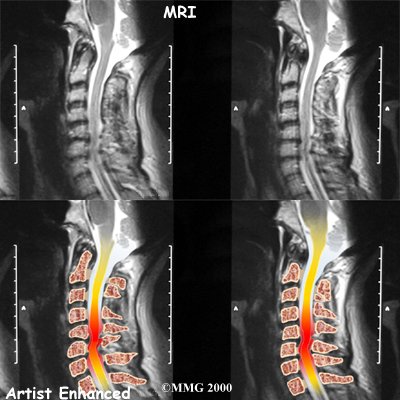

The magnetic resonance imaging (MRI) scan uses magnetic waves to create pictures of the cervical spine in slices. The MRI scan shows the cervical spine bones, as well as the soft tissue structures such as the discs, joints, and nerves.

MRI scans are painless and don't require needles or dye. The MRI scan has become the most common test to look at the cervical spine after X-rays have been taken.